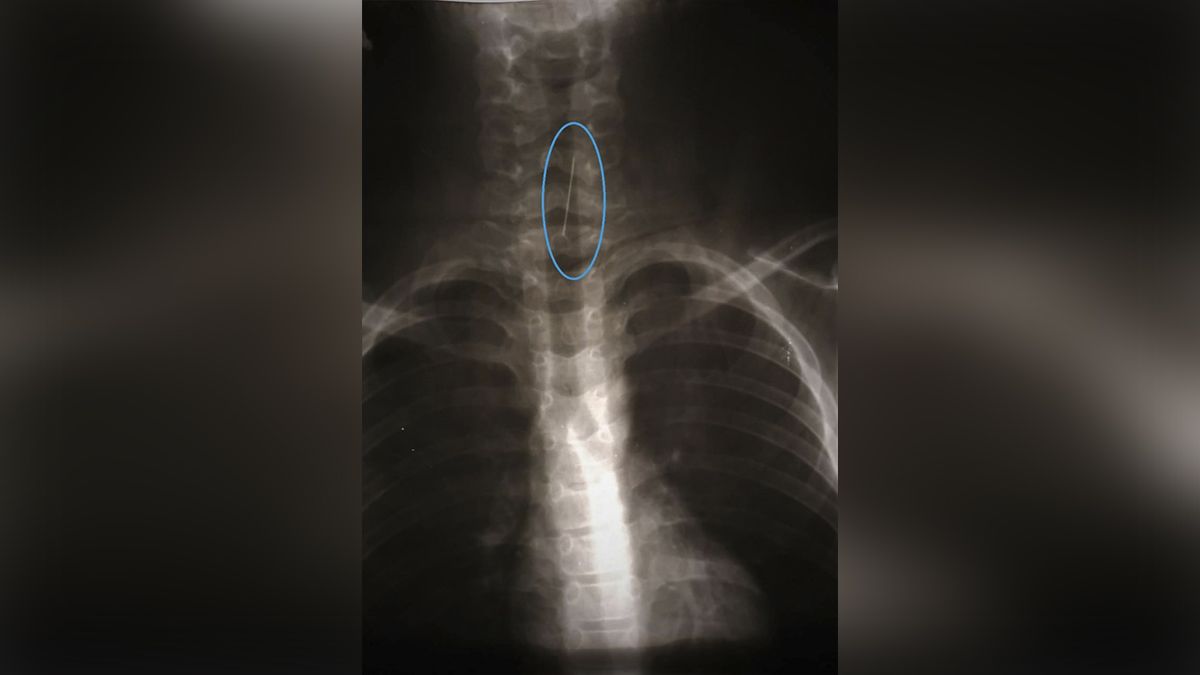

После эндоскопического исследования медики обнаружили портняжную булавку, которая подкололась к трахее. При попытке удалить предмет с помощью специальной петли инородное тело начало мигрировать вниз по дыхательным путям к правому, меньшему по диаметру, бронху. Ситуацию усложняло и то, что булавка спускалась головкой вниз, подкалываясь к сегментарному бронху. Малейшая неосторожность могла привести к осложнениям в виде травмы бронха или кровотечения. Поэтому специалистам пришлось искать нестандартное решение ситуации.

"В результате тщательного обсуждения, просчитав разные варианты развития событий, принимаем крайне нестандартное решение - ввести через жесткий бронхоскоп гибкий бронхоскоп и попытку удаления постороннего тела из сегментарного бронха. После осторожных и медленных манипуляций нам удается удалить злосчастную булавку из дыхательных путей маленького пациента, почти не травмируя слизистую ни бронха, ни трахеи. И самое главное! Слаженные действия всей нашей команды высококвалифицированных специалистов позволили избежать большого оперативного вмешательства", - пишут медики.